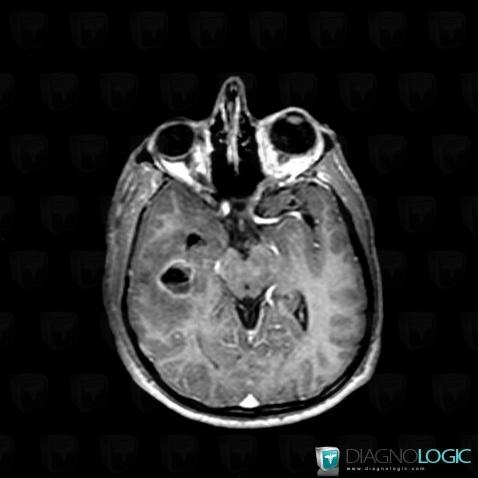

Abscess, Cerebral hemispheres, MRI

Here is the specific information in the key image above:

- Diagnosis Abscess, Location(s) Cerebral hemispheres, with gamuts Temporal lobe T2WI or FLAIR hyperintense lesion, Intracerebral T2W or FLAIR hyperintense lesion